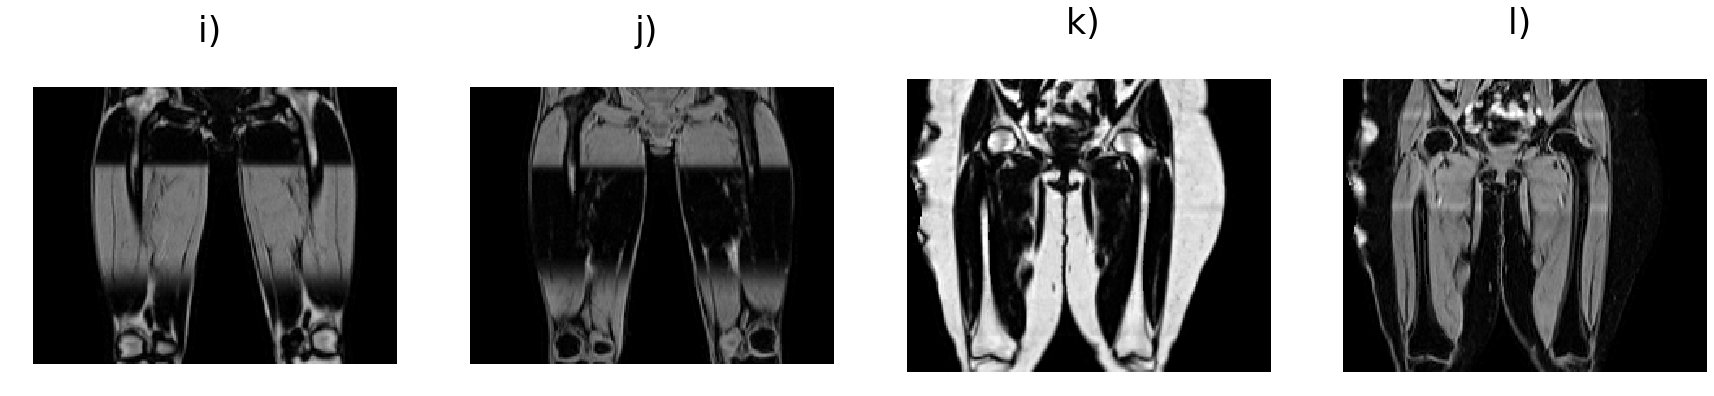

Fig. 3 shows the ground-truth data, predictions and their absolute difference for the fat and water channels of a participant in the testing set. Model predictions and the original data from the scanner for participants affected by various fat-water swaps are provided in Fig. 4. The examples were selected to illustrate the performance of our model in a variety of scenarios: data that are not affected by major swaps, data affected by swaps that cover an entire series in the acquisition (Fig. 4 a, c), as well as data displaying complex partial (Fig. 4 b, d, e) and/or boundary swaps (Fig. 4 f, g). The absolute difference images in columns 3 and 6 of Fig. 4 highlight where the original data have been affected by a fat-water swap in the scanner reconstruction but the model correctly predicted the fat and water channels. Fig. 5 provides examples of 3D segmentations using data that suffered from fat-water swaps (top row) and the segmentation when using our model predictions (bottom row) for the following organs and tissue (from left to right): abdominal subcutaneous adipose tissue, left kidney, spleen, and left/right iliopsoas muscles (red and green, respectively). The predictions shown in Figs. 3 and 4, as well as the underlying volumes used for the 3D segmentations in Fig. 5, are outputs of the final dual-input model, which performed the best across all of our experiments.

We have shown that our single- and dual-input models are able to predict swap-free fat and water volumes. Processing the entire neck-to-knee volumes, for example those found in the UK Biobank abdominal protocol, takes approximately eight seconds per scan. We have established the high quality of our results through quantitative metrics such as PSNR and SSIM (with average values consistently ) for the dual-input model in both cross-validation experiments (Table 1) and out-of-sample test data on final versions of the models (Table 2). We have shown qualitative performance on scans where the scanner software failed to adequately separate the fat and water channels during reconstruction in visual examples (Fig. 3) and by comparing to dixonfix to establish our method does not induce fat-water swaps (false positives). As a final qualitative validation we used the predicted channels as input to 3D segmentation models and have shown how the corrected data produces superior segmentations.